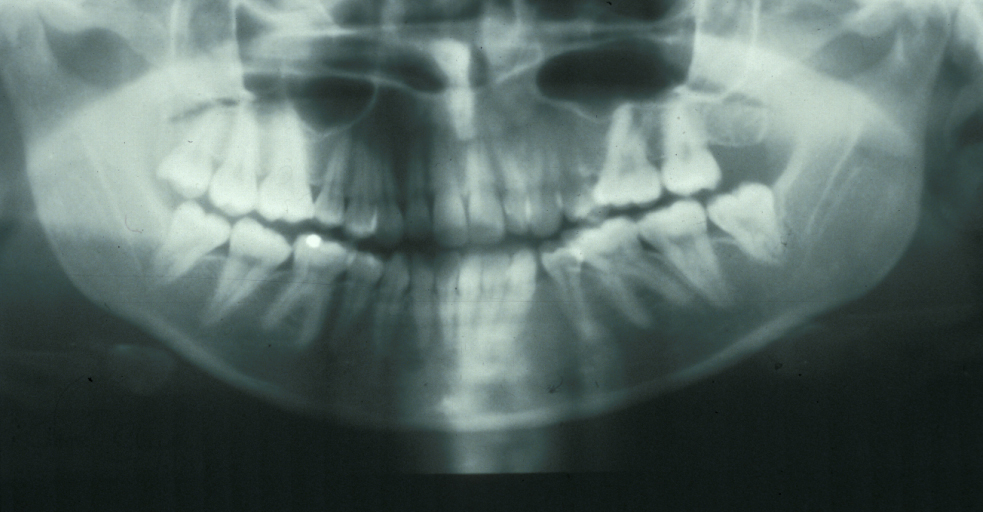

Figure 2 and Figure 3 illustrate examples of indications for removal of a third molar tooth.

Assessment of the tooth is both clinical and radiographic. If somebody presents in pain, it is important to establish that this is coming from the third molar and not elsewhere. Pain is often vague, poorly localised and may be referred from another tooth, or as part of facial arthromyalgia (condition affecting the jaw joint). A dental panoramic radiograph is ideal as it helps to assess all the teeth at once. The health of the adjacent molars may influence the decision whether to remove the third molar or not. Large crowns or old restorations are all at risk of dislodgement during surgery. It is also worth considering whether alternative treatment options are available. For instance, pericoronitis due to an over-erupted upper third molar may be dealt with by extracting that tooth only, with or without operculectomy. In the presence of other teeth of poor prognosis, will it be better in the long term to save the third molar which may be used as a denture or bridge abutment in the future?

These points help to determine whether the tooth can be simply elevated or will need a surgical approach. A series of radiographs depicted in Figure 4 to Figure 8 illustrate these points further.